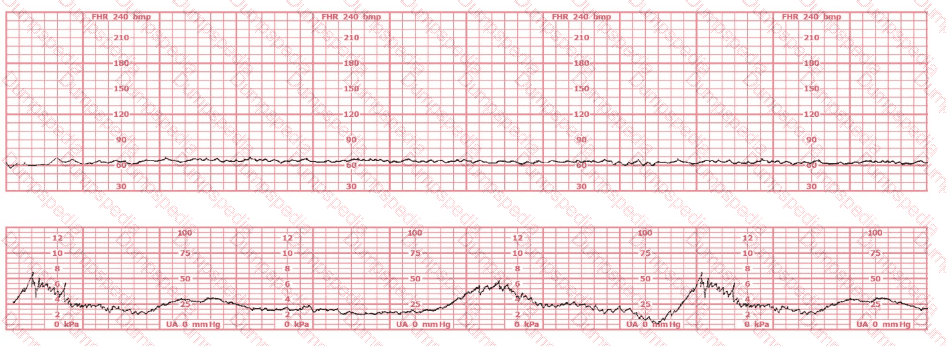

The tracing shown is from a woman at 28-weeks gestation in the post-anesthesia care unit (PACU) after an appendectomy. She is alert and awake. Based on this fetal heart rate pattern, the most appropriate intervention is: